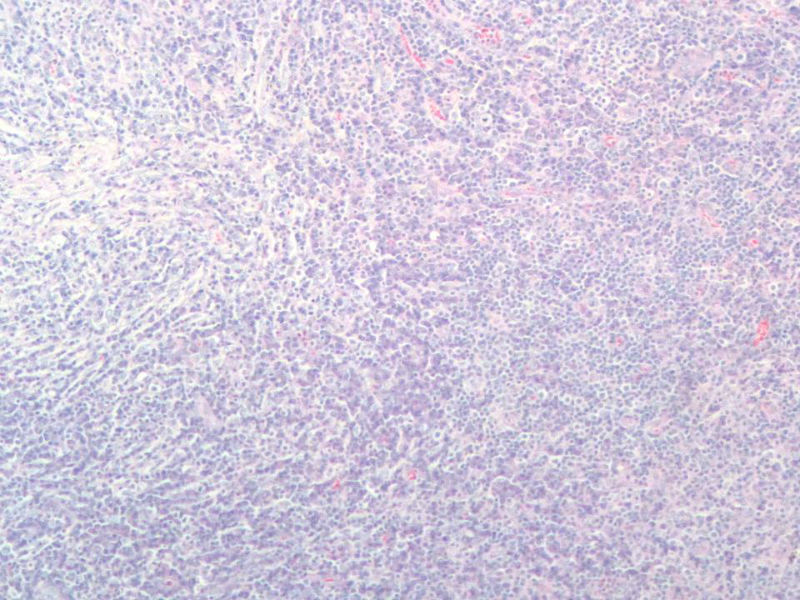

女,56岁,右颌下肿块两月余,检查肿块活动度差,手术切除。肉眼,灰白类圆形肿物,2X2X1厘米。包膜不完整,切面灰白色,质软。

与经治医生交流,患者目前一般状态良好,体表未触及肿块,CT各主要器官未见病变。结合免疫组化,我们考虑为浆细胞肉芽肿,但这个部位发生罕见,请指点!谢谢!

能产生显著淋巴滤泡的一些病变在很多专著甚至教科书中都有比较一致的描述。浆细胞肉芽肿的概念本身就有很多争议,WHO呼吸系统和软组织分册均将其归为炎性肌纤维母细胞瘤的同义词,似乎强调梭形细胞在其诊断中的意义。如果浆细胞肉芽肿是最合适的名称的话,那也是少见病例发生在少见部位并有不典型的形态学表现。

另外,网络读片不能完整地看到肿块的结构,肿块能否定是淋巴结吗?如果是淋巴结,我个人没有淋巴结浆细胞肉芽肿的读片经验,能不能考虑或排除一下浆细胞型的castleman或其它?